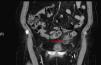

Se realizó ecografía abdominal urgente no objetivándose hallazgos patológicos, por lo que ante la disociación clínico-radiológica-biológica se optó por realizar TC abdominal con contraste y posteriores reconstrucciones multiplanares. La TC reveló la existencia de una lesión ovoidea bien delimitada, de densidad grasa con halo periférico que se realzaba con el medio de contraste (reacción inflamatoria) en íntimo contacto con la pared del colon sigmoideo a nivel pélvico y que se acompañaba de infiltración de la grasa del meso adyacente. La pared del colon sigmoideo era normal. No se observó líquido libre intraabdominal. Todos estos hallazgos eran muy indicativos de AE (fig. 1).

La TC muy extendida ya como herramienta en el diagnóstico del dolor abdominal agudo de urgencias es la prueba más sensible y específica ofreciendo hallazgos patognomónicos. Éstos incluyen la visualización de una imagen ovoidea de densidad grasa que corresponde al apéndice inflamado dependiendo de la serosa del colon, rodeado de una fina imagen lineal de 1-2mm de grosor y con halo de tejido adiposo denso en forma de estrías o bandas. Puede existir o no engrosamiento del peritoneo parietal y/o de la pared del colon.